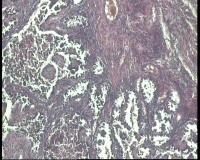

| 性别 | 女 | 年龄 | 53岁 | 临床诊断 | 右侧卵巢囊肿 |

| 一般病史 | 彩超:盆腔可见囊实性回声,囊性为主,大小约5.0x3.7厘米,其内可见分隔回声,部分分隔内回声不纯净,形态欠规整 | ||||

| 标本名称 | 腔镜下右侧卵巢囊肿手术 | ||||

| 大体所见 | 囊壁样组织5.5x5.0厘米,4.5x2.5厘米2块,壁厚0.1-0.2lm,囊壁大部分光滑,局灶见0.7x0.5x0.3厘米淡黄色突起组织,另见淡黄色、肉粉色质软组织2.8厘米一堆。 | ||||